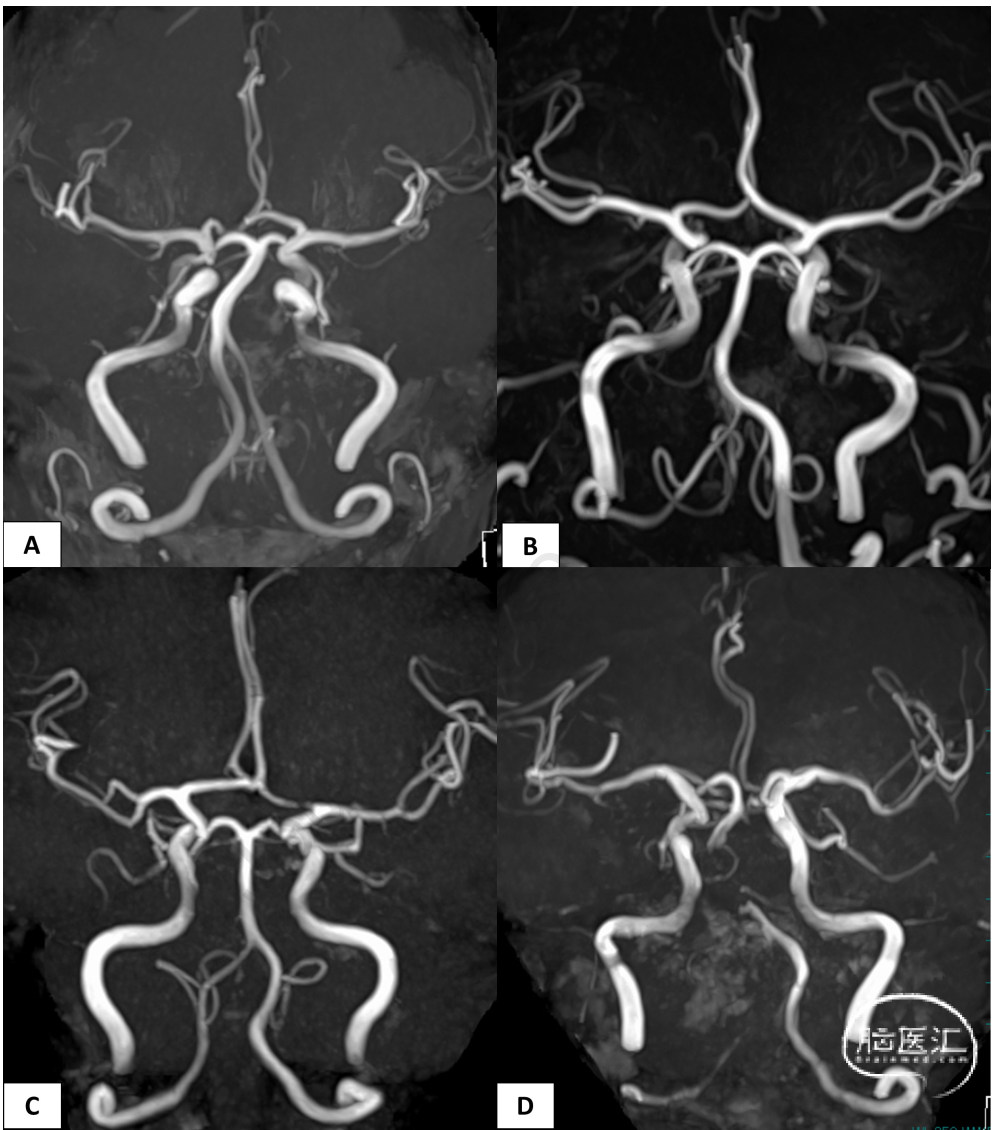

图2. 显示了对称情况(A)和不对称情况(B-D)

A)分叉模式、早期皮质分支的有无、M1的长度和走形都是对称的。B)右侧 MCA 为三叉型,左侧 MCA 为双叉型。C)右侧 M1被归类为短M1,左侧M1被归类为长M1。D)右侧M1的走形路线向下,左侧M1的走形路线向上。